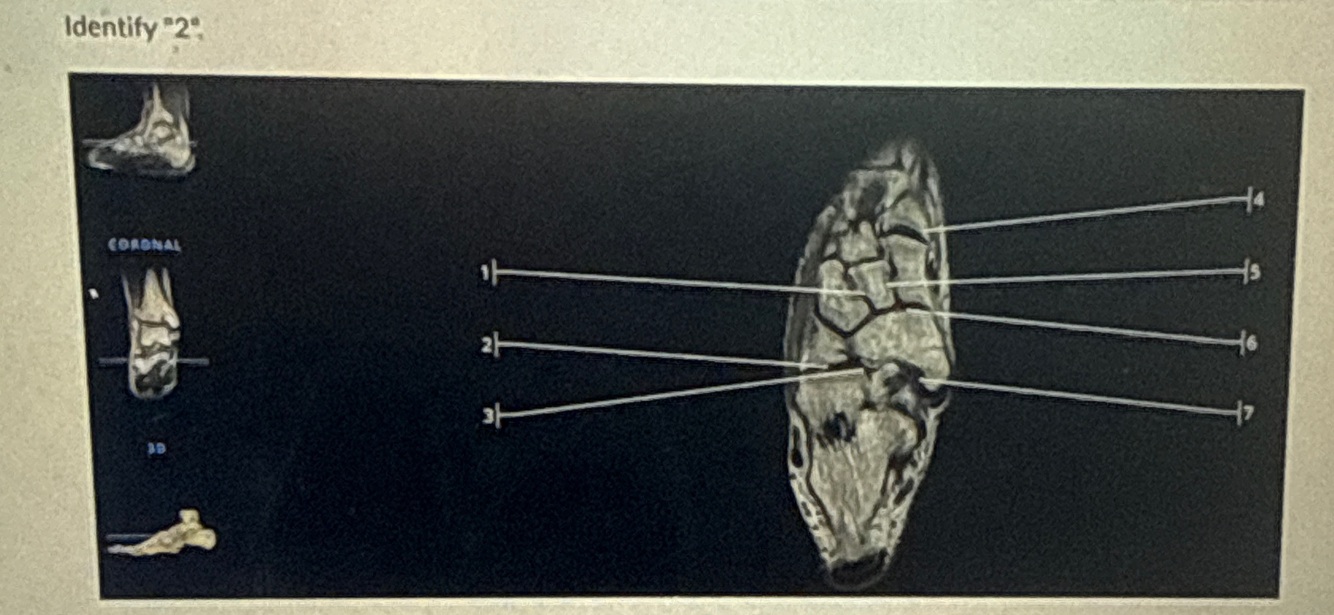

4

Q

A

Tibialis anterior tendon